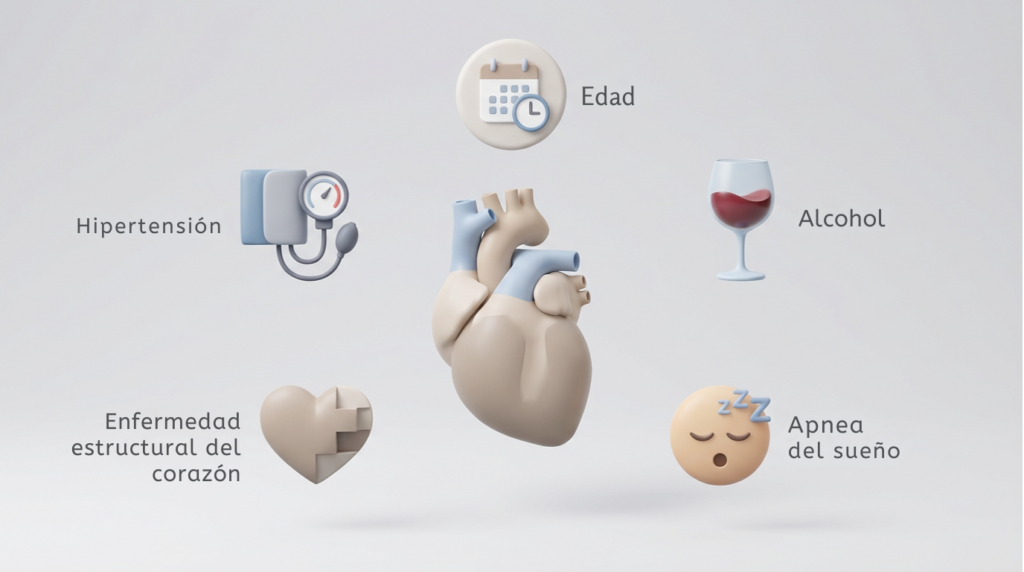

¿Por qué ocurre la fibrilación auricular?

La FA no aparece por azar. Se asocia a:

- Hipertensión arterial

- Envejecimiento

- Enfermedad estructural del corazón

- Apnea del sueño

- Consumo excesivo de alcohol

- Predisposición genética

- Contagio por SARS-CoV-2 (COVID-19)